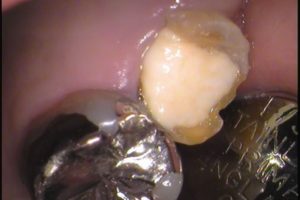

初診時のお口の中は・・・

このような状態です。

根管治療の途中なので、歯の中に白い仮蓋がしてあります。

仮蓋を外してみると・・・

歯の中は黒く、良い状態ではありません(^^;

残っている歯は割れてはいなかったので、

当院で治療を進めました。